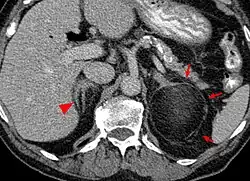

An adrenal myelolipoma | |

Most myelolipomas are unexpected findings on CT scans and MRI scans of the abdomen. They may sometimes be seen on a plain X-ray films.[4]